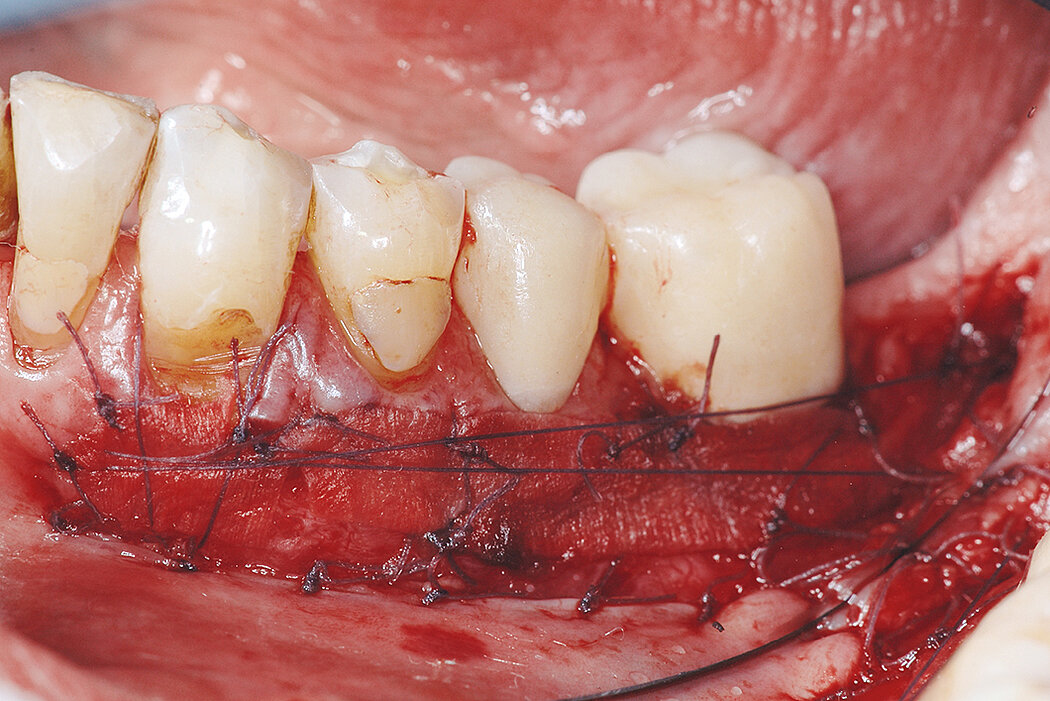

角化组织增宽

临床挑战

修复体周围的角化组织增宽

目标

增加修复体周围的角化组织宽度,避免自体软组织移植导致的患者不适。

结论

Mucograft®(原型样品)*和结缔组织移植(CTG)一样,可有效地、可预期性地增宽角化组织。3D基质显示了优异的可操作性,在开放式愈合情况下也可获得成功,和CTG比起来显著减少患者不适及手术时间。